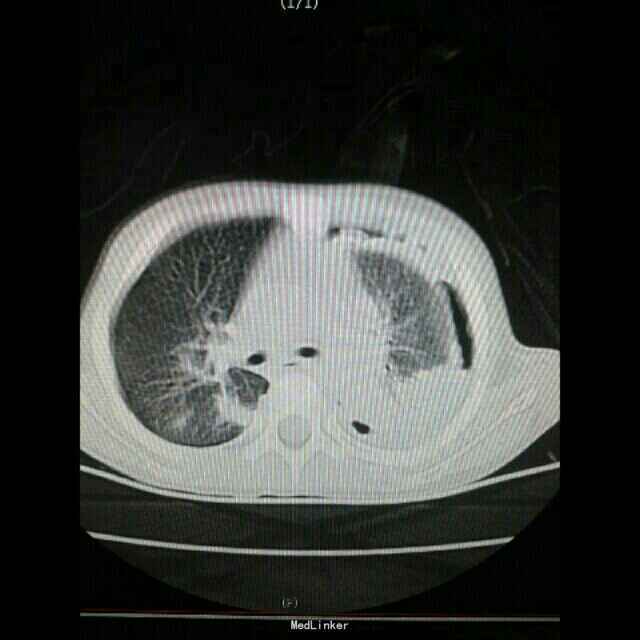

患儿,女,3岁10月。因发热5天,咳嗽4天入院。 患儿于入院前5天出现发热,热峰39摄氏度,发热周期5-6小时,自行口服头孢类药物治疗,病情无好转。来医院就诊,住院治疗。

状态可。左肺听诊呼吸音减弱,叩诊浊音。右肺呼吸音粗糙,叩诊清音。

初步诊断:1.急性支气管肺炎 2.胸腔积液(性质待查) 入院完善相关检查,静滴美罗培南及万古霉素抗感染治疗,病情无好转。入院5天,病情加重,复查血常规及肺CT较入院时加重。转入胸外科治疗,行手术治疗,术中引出大量脓液。修订诊断:1.急性支气管肺炎2.脓胸。

目前治疗中,术后体温趋向平稳,病情好转。